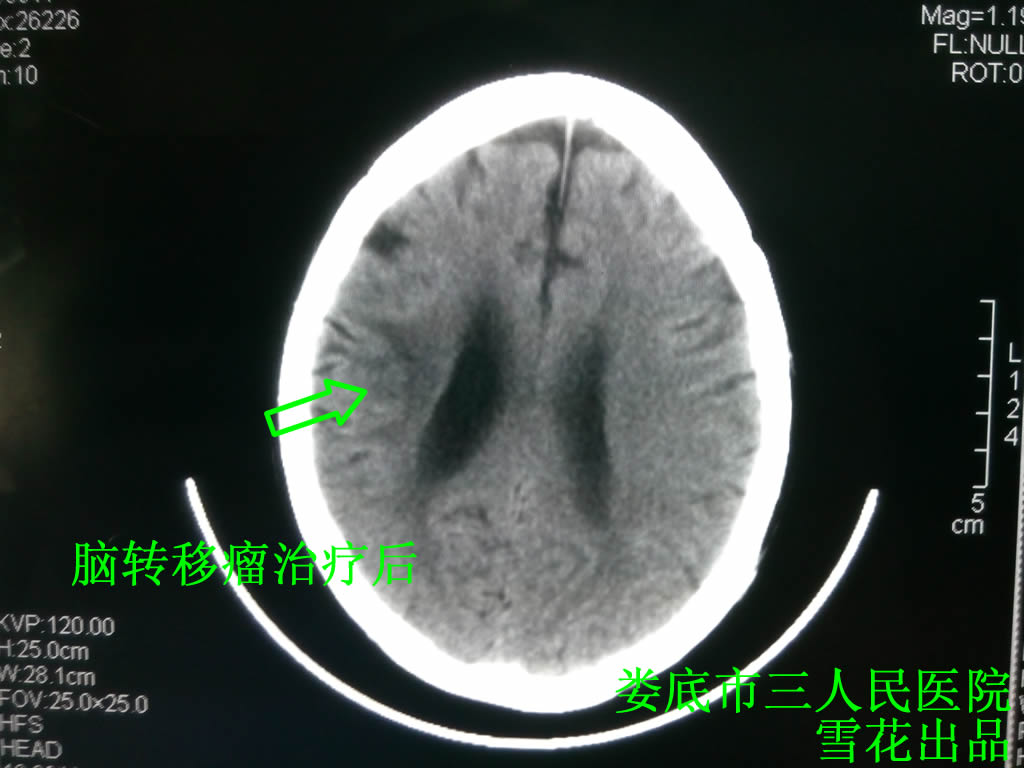

口服中药5剂后患者头痛有所好转,待取得患者一定的信任后,又多次建议患者行全颅放疗,患者终于答应,但要求放疗不能超过10次,给予全颅放疗30 Gy/10次,放疗后患者头痛明显好转,查头部CT示右额叶占位明显好转(见图三),但患者对治疗并不十分满意,因为放疗照射野区域的头发不断脱落,建议化疗,患者坚决拒绝,推荐试用靶向药物易瑞莎,(因患者拒绝基因检测,所有未行相关检查),口服易瑞莎1月后患者头痛消失,咳嗽也明显好转,查肺部CT示较前好转(见图四),建议患者坚持口服易瑞莎及中药,在之后的1年里患者一般情况良好,但1年后无明显诱因出现左侧肢体阵发性刺痛,查头部及肺部CT示较前无明显变化,照片及相关检查未见明显异常,结合临床仍考虑肺癌骨转移,因为患者拒绝放化疗,所以仅给予口服止痛药,治疗有效,现患者已追踪观察2年,头部及肺部病变未见复发。